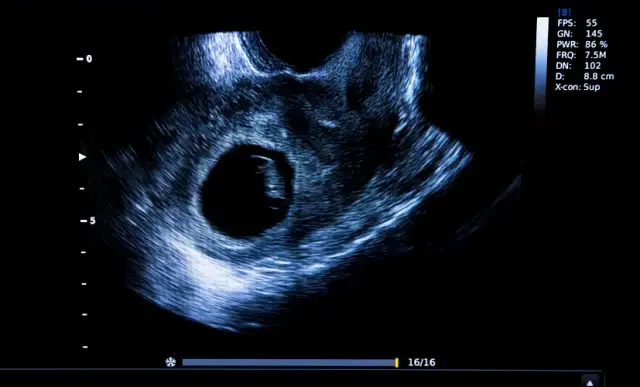

Kiedy USG dopochwowe potwierdzi ciążę? Tydzień po tygodniu

Sprawdź, kiedy USG dopochwowe potwierdzi ciążę. Dowiedz się, co widać tydzień po tygodniu, jak beta-hCG wpływa na widoczność i co robić, gdy ciąży nie widać.

USG w 5. tygodniu ciąży: Sprawdź, co zobaczysz, kiedy brak zarodka niepokoi i jakie objawy są normą. Rozwiej obawy i poznaj fakty!